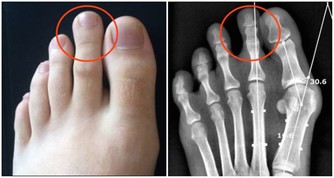

2.右側臉頰特別是顴骨處發紅,為肺有熱病,但是在未發將發之時。

3.肺初病者,特別是初受風邪,在面部再現為兩眉上發白。

4.喘息鼻張者為肺病已久。